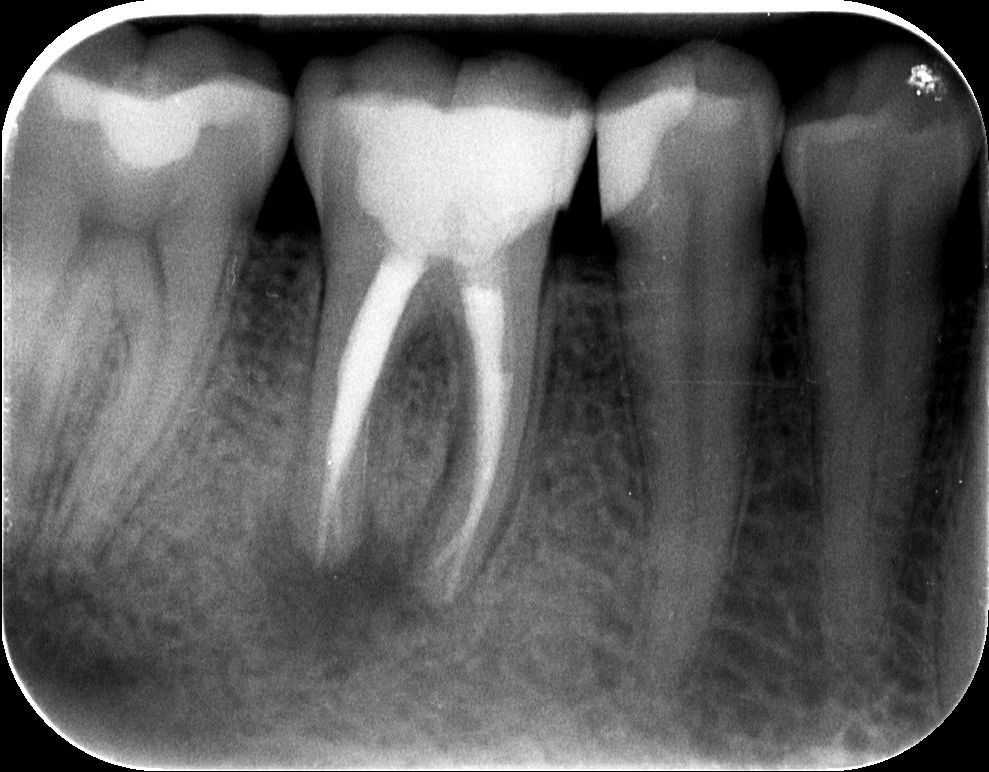

A teljes, kész gyökértömés, illetve az üvegszálas csap beragasztása után készült a felvétel. A csapos megerősítésre sajnos azért volt szükség, mert a fog koronájának jó része hiányzott. Ilyenkor a maradék foganyag védelme érdekében vagy öntött, vagy üvegszálas csapot helyezünk a fogba.

mikroszkópos gyökérkezelés 4. kép

3 hónapos kontrollfelvétel. A gyógyulás még nem teljes, de már egyértelműen látható a kedvező folyamat. A kiinduló képen megfigyelhető, hogy a gyökércsúcsok körül lévő elváltozás, az a jellegzetes fekete árnyék már halványodik, a gyulladás helyét egyre jobban az ép csont tölti ki.

mikroszkópos gyökérkezelés 5. kép